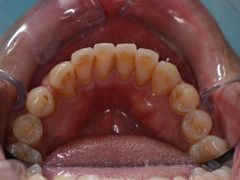

• 新达口腔(华东理工大学店)

• -新达口腔(华东理工大学店)